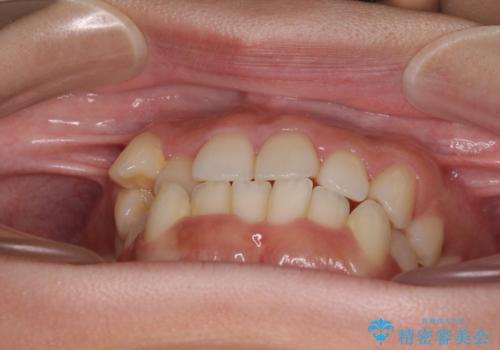

上顎歯列が下顎の歯列に対して狭小であり、一部下顎の奥歯が上顎よりも外側に位置している状態でした。

上顎の急速拡大装置を使用して上顎骨を側方に拡大することで上顎歯列を拡大し、下顎歯列も拡大できるようにすることで、歯列を整えることとしました。